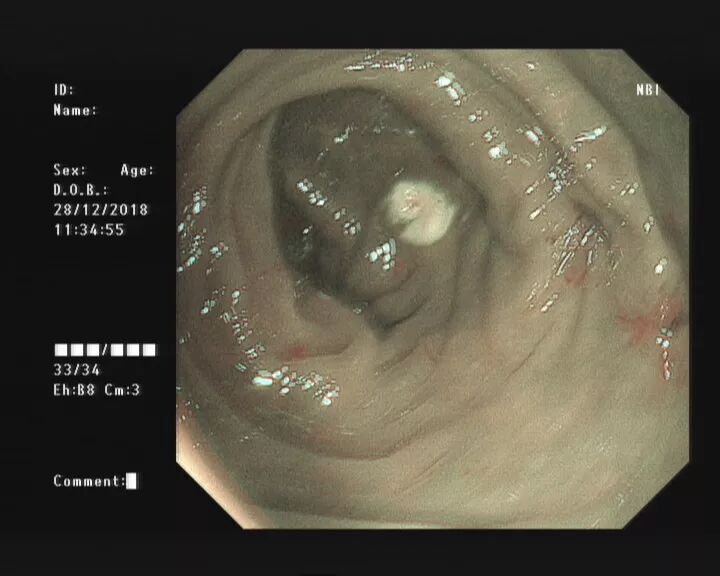

当黄斑马导丝及导管置入阑尾腔时,可见脓性分泌物涌出。

随之进行阑尾腔冲洗;